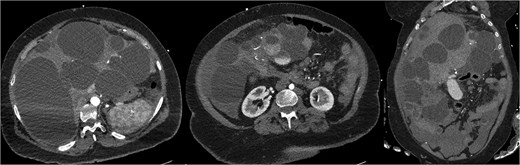

CT mesenteric angiogram (CTMA) revealed no active contrast extravasation but showed large volume haemoperitoneum consistent with a ruptured hepatic cyst, suspected to arise from segment 4b (Fig. 1). The patient was stabilized with broad-spectrum antibiotics, three units of packed red blood cell transfusions and transferred to ICU. Interventional radiology performed prophylactic embolization of segment 4b arteries with concurrent drainage of large-volume blood-stained ascites.

CTMA with axial and coronal views demonstrates a massively dysmorphic polycystic liver with haemoperitoneum and heterogeneously hyperdense material near inferior aspect of liver.